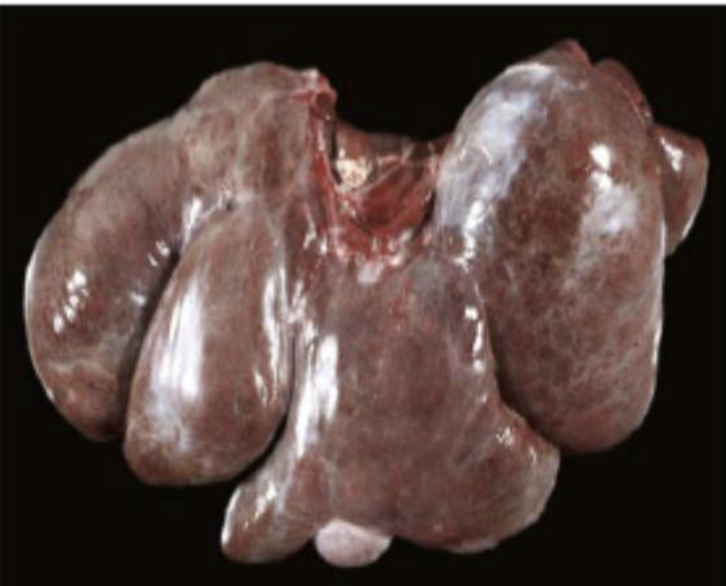

how does passive congestion appear grossly?

lobes of liver are enlarged with rounded edges

what does the image show?

passive congestion